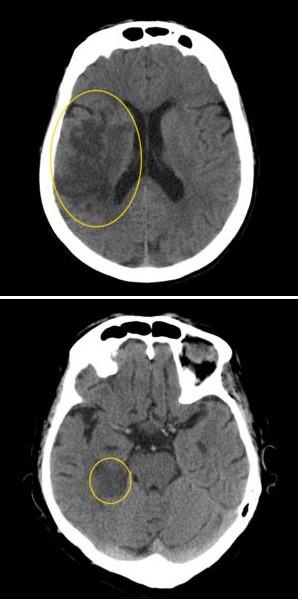

|

| Ишемический инсульт на МРТ головного мозга |